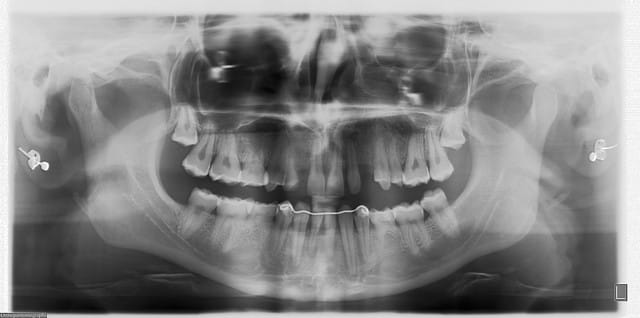

dentiste57

17/06/2009 à 15h43

jeune homme,

18 ans,

agénésie de 12,

extraction de 52 depuis 2 ans et remplacement par un mainteneur d'espace, vient consulter pour un implant...

j'adore ce genre de cas, c'est un vrai défi esthétique où on a pas le droit à l'erreur.

je pense qu'une greffe osseuse serait peut être nécessaire pour la concavité. Toutefois, je devrais pouvoir m'en sortir en dilatant la crête osseuse vestibulaire pendant la pose de l'implant.